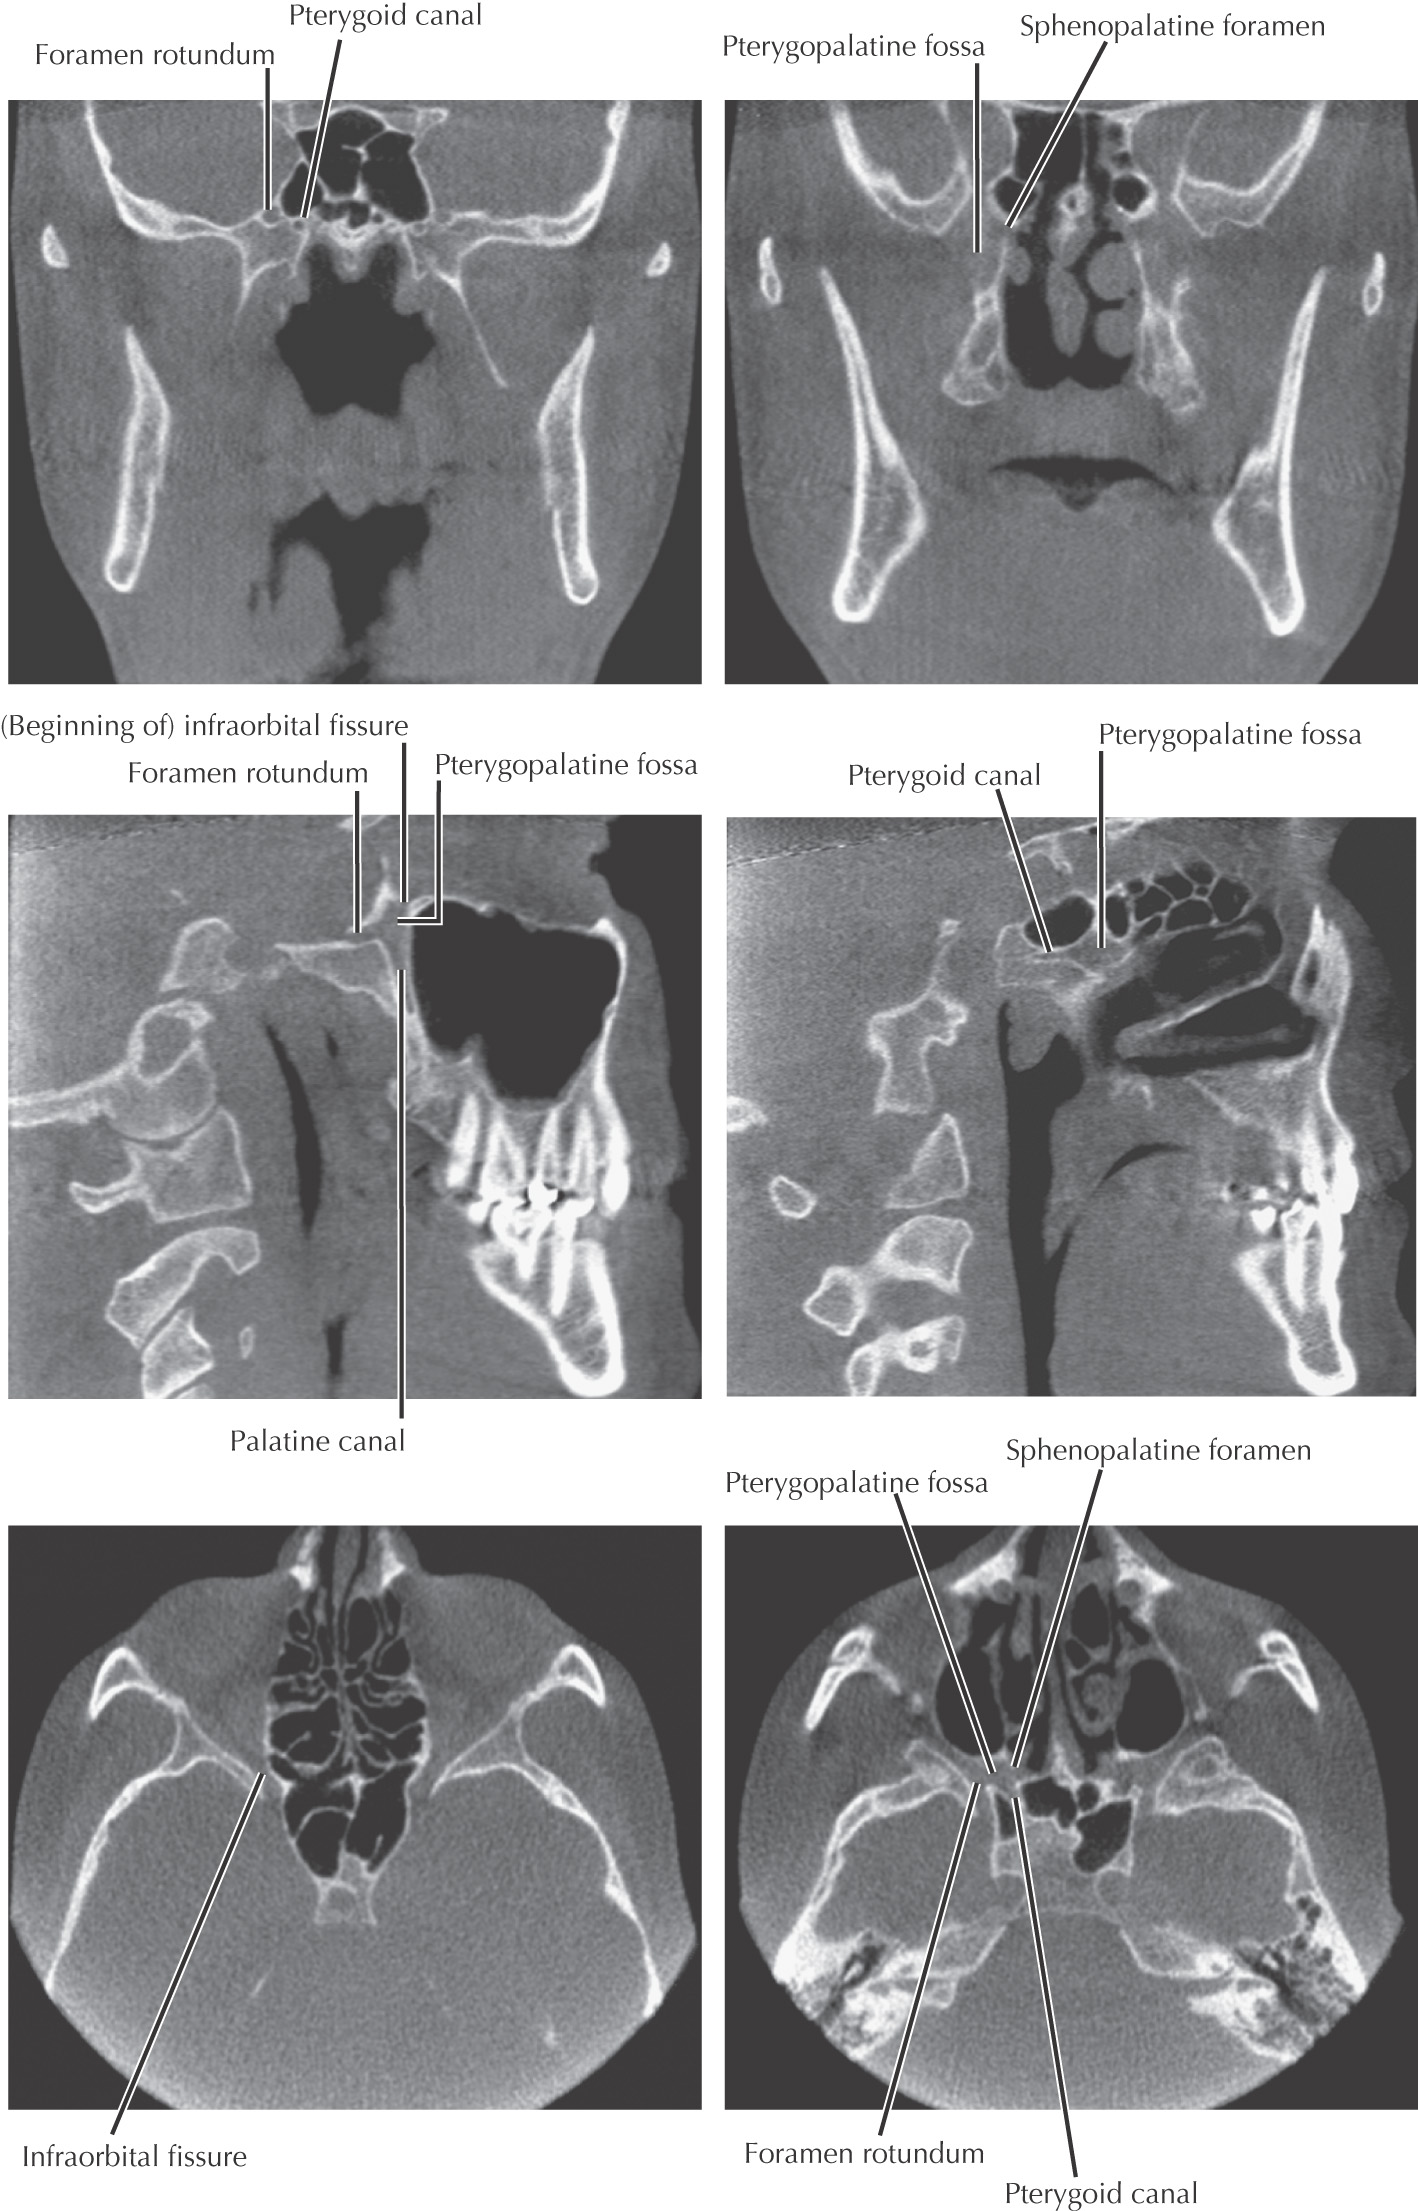

Pyramid-shaped fossa on the lateral aspect of the skull between the maxilla’s infratemporal surface and the pterygoid process of the sphenoid

Contains major nerves and blood vessels that supply the nasal cavity, upper jaw, hard palate, and soft palate: the maxillary division of the trigeminal nerve, pterygopalatine (sphenopalatine, Meckel’s) ganglion, and 3rd portion of the maxillary artery

Allows the infratemporal fossa, middle cranial fossa, foramen lacerum, nasopharynx, nasal cavity, orbital cavity, and oral cavity to communicate

7 foramina/fissures allow passage of nerves and vessels